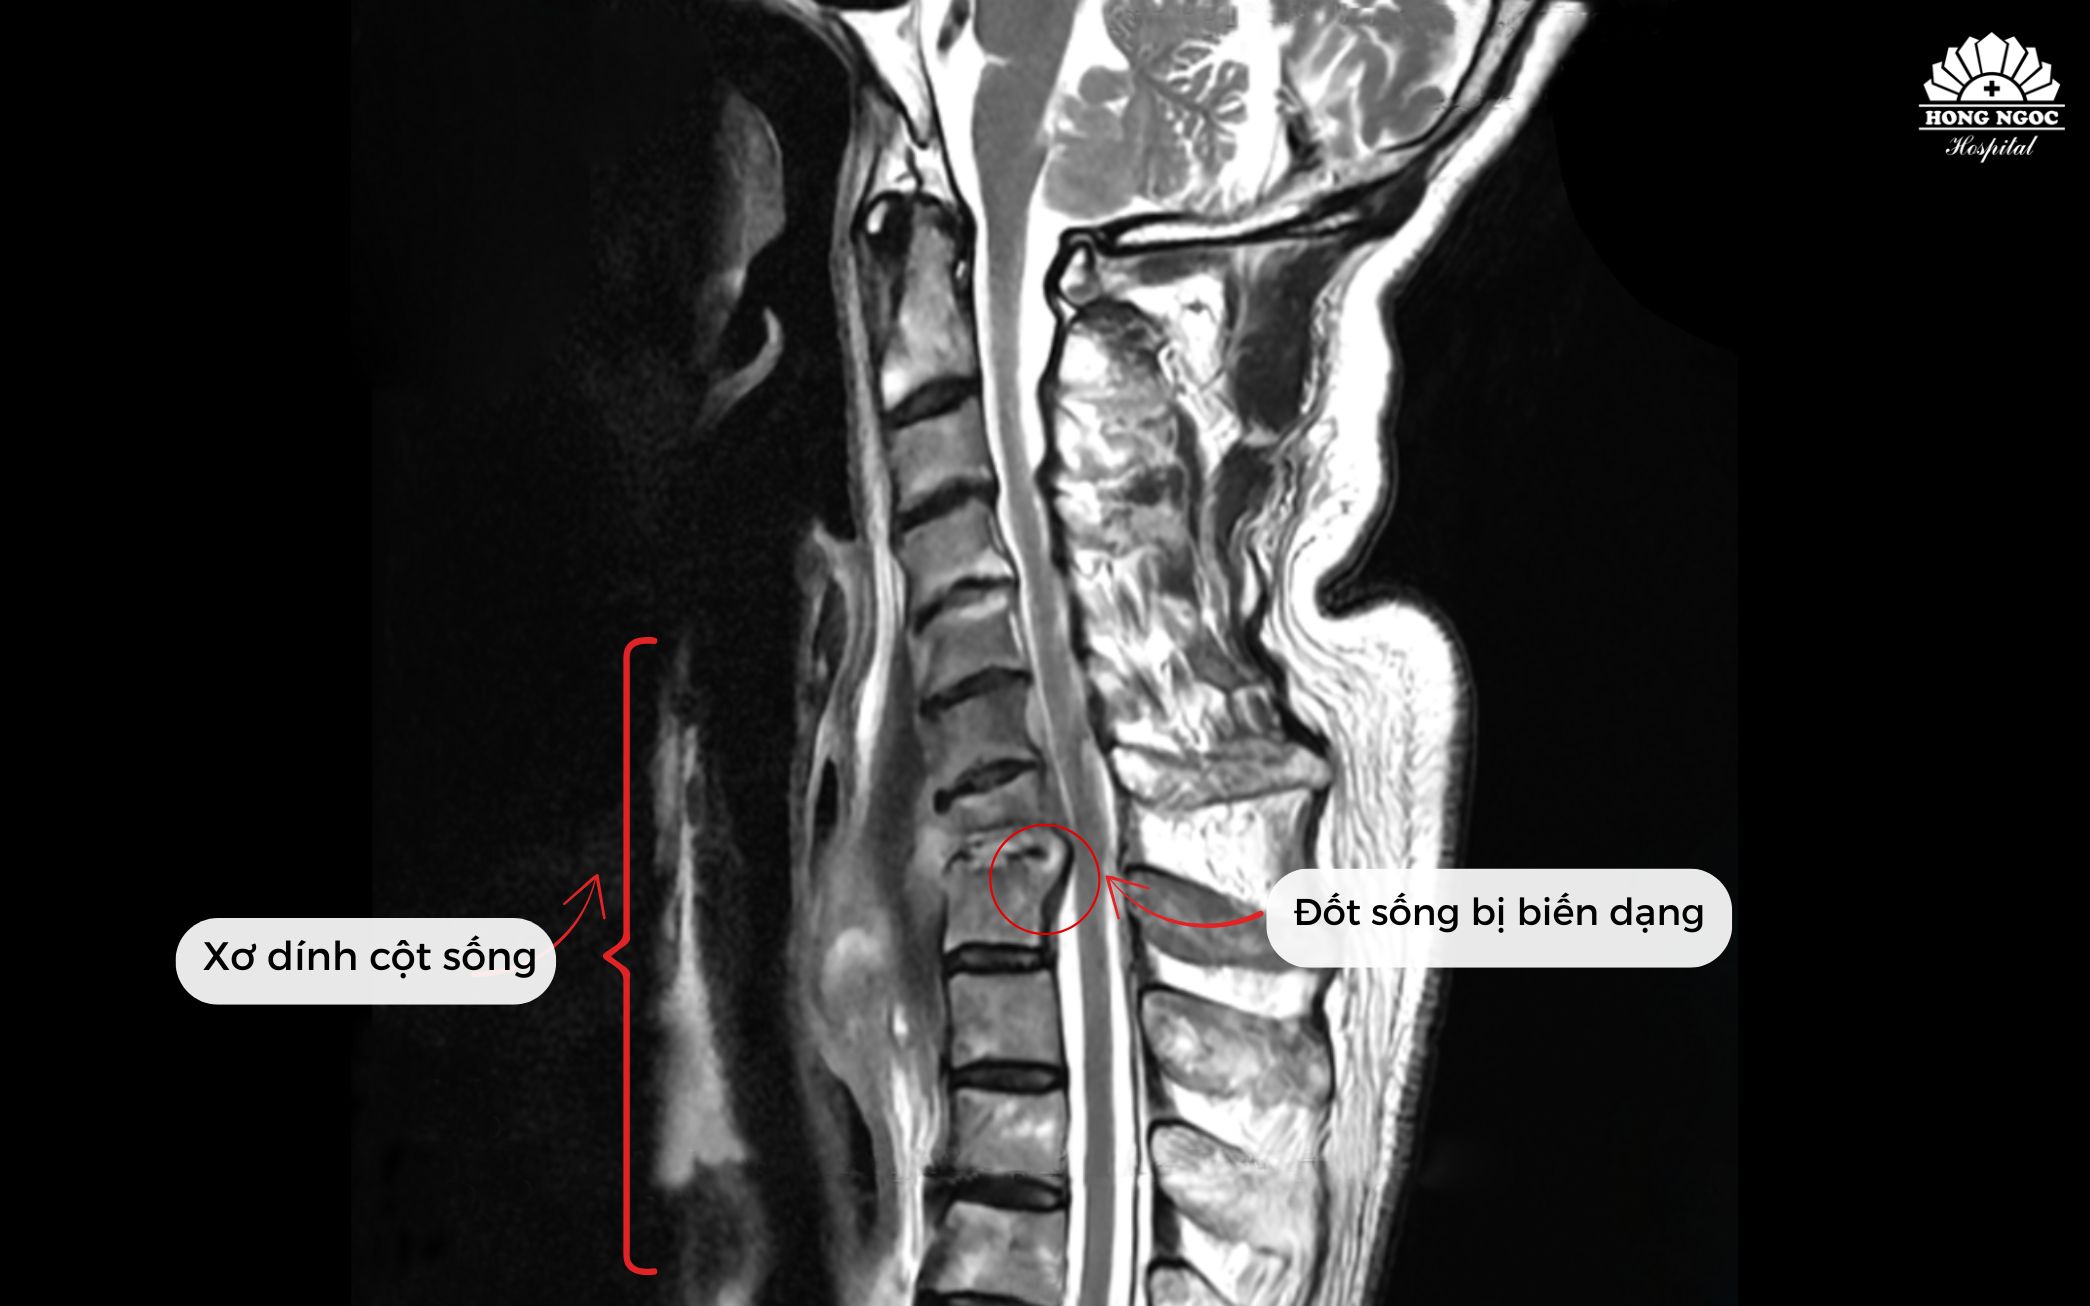

수술 전 섬유화 및 변형된 척추뼈 상태

하 부교수는 "이는 전 세계 의학 문헌에서도 드문 경우로, 근골격계 감염 사례의 약 2~7%에 불과합니다. 원인은 외상, 수술 후 합병증 또는 혈액을 통한 감염일 수 있습니다"라고 설명했습니다. 염증과 농양이 C7/T1 척추체와 추간판을 파괴하여 섬유성 띠를 형성했고, 이로 인해 환자의 목이 항상 굽혀져 있어 돌리거나 젖힐 수 없는 상태였습니다. 조속히 수술하지 않으면 운동 마비 위험이 매우 높은 상황이었습니다.